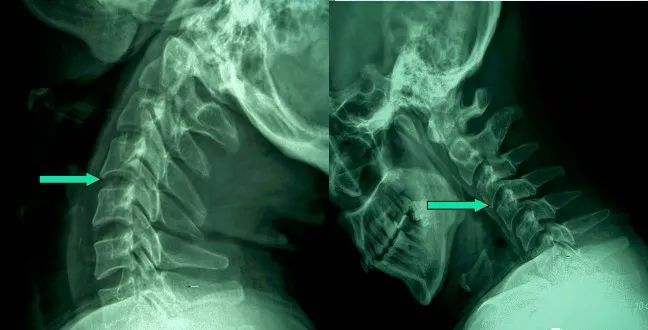

1、頸椎移位

由于頸椎關(guān)節(jié)突間關(guān)節(jié)面近乎水平位,一旦椎間盤發(fā)生退變、椎間隙即變窄,關(guān)節(jié)囊及韌帶松弛,加上頸部活動(dòng)時(shí)重力的影響,即可造成積累性損傷,加速頸椎退變和不穩(wěn),導(dǎo)致頸椎關(guān)節(jié)發(fā)生移位,使椎間孔變狹,椎管徑發(fā)生改變,壓迫神經(jīng)根或脊髓,產(chǎn)生臨床癥狀與體征。